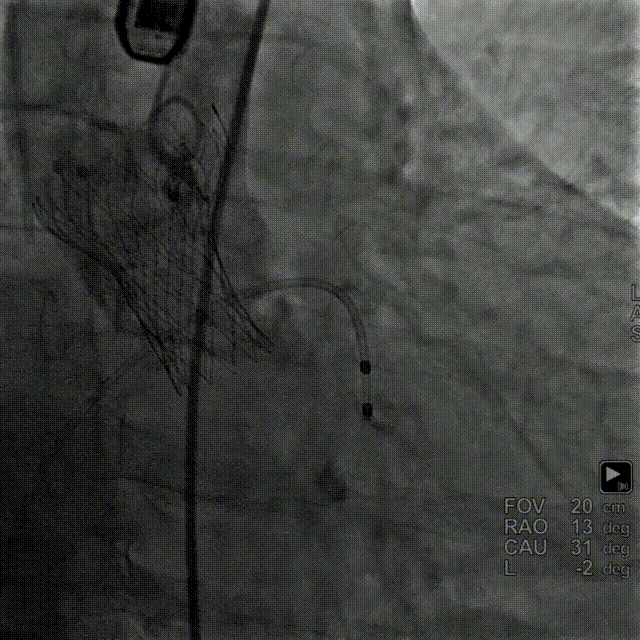

TaurusElite 输送器轻松过弓、跨瓣,TaurusElite AV26瓣膜高位释放。

TaurusElite轻松过弓

瓣膜释放